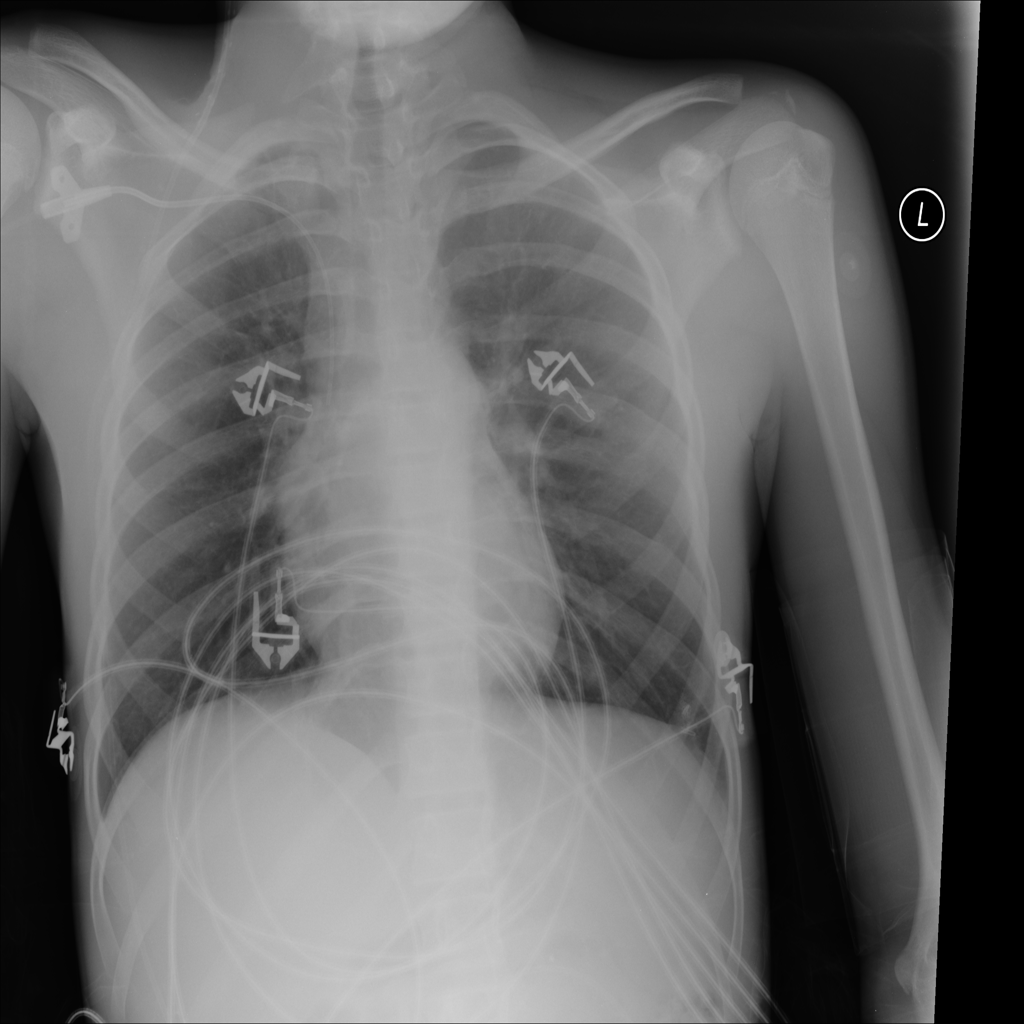

Mass

A mass is a larger focal opacity or lesion seen on the image. It is a descriptive finding that can have several causes and usually needs more imaging or clinical context to characterize.

PAT-C0E5 · IMG-001Mass

PAT-C0E5 · IMG-001

PA